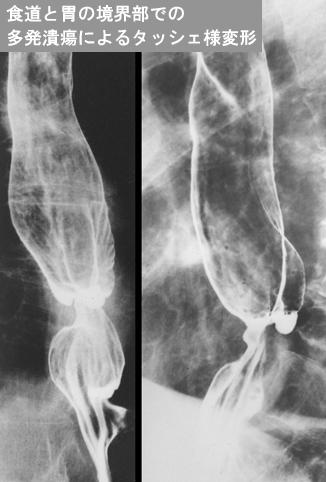

症例提示(所在地,施設名等): 東京都・ 国立がんセンター中央病院と九州がんセンターの共同作成

症例登録日 2014/02/28

画像ID:12206